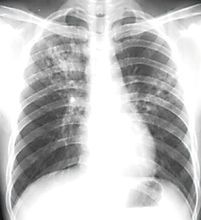

肺部圖片及養肺食物(1)根據病情恢復情況和體力,選擇適當項目進行鍛鍊,如氣功、呼吸操,散步、太極拳等。

肺熱圖片咳嗽雖然是孩子最常見的症狀,但是如果你的孩子經常咳嗽、反覆咳嗽、咳嗽老不好,那很可能是“肺熱”惹的